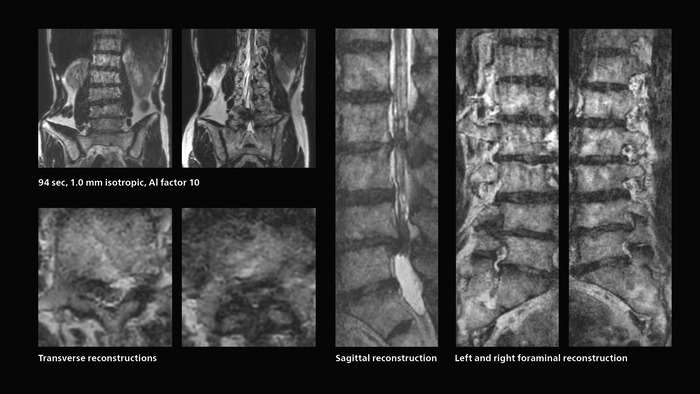

Fast lumbar spine imaging for successful exam of patient in pain

A patient arrived saying that undergoing MRI was not possible because of severe back pain and leg pain, was imaged with SmartSpeed in only 94 seconds. The scan was diagnostic and afterwards the patient confirmed that it only took a little while. Performed on Elition X.

Fast lumbar spine MRI with SmartSpeed of a patient in pain produced a successful isotropic diagnostic scan in only 94 minutes.

The hospital’s fast lumbar spine ExamCard includes T2W SpineVIEW, 1:40 min, 1.0 mm isotropic, acceleration factor 12.

Also in dynamic MRI of the liver Dr. Katahira sees important improvements. While previously his scan used 9 seconds for a 5 mm slice, SmartSpeed now allows him to achieve a thin slice volume scan (1.6 x 2.1 x 2mm) with double arterial phase using acceleration factor 8. He indicates this is very useful for the radiologist when diagnosing, especially because it can provide a high temporal resolution.

Dynamic MRI of liver using SmartSpeed

A patient was referred for MR imaging of HCC. A double arterial volume dynamic study was performed. Since it is a volume dynamic study, it can also be evaluated using MPR images. Performed on Elition X.

Fast dynamic liver MRI: volume dynamic study of 1.05 min, 1.6 x 1.8 x 2.0 mm, 200 slices

The hospital’s routine ExamCard for dynamic MRI of the liver uses total scan duration 1:05 min, dynamic scan time 9.2 sec, 1.6 x 1.8 x 2.0 mm, 200 slices, acceleration factor 8.